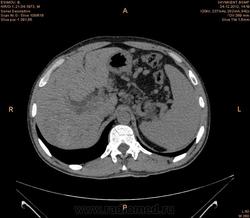

Предварительно образование головки ПЖ, и в печени. Что с ферментами?

на операций рак головки подж.железы с метастазир. печень.

инфильтрация тут нисходящей 12 перст кишки , расширенного холедох,расширенный вирсунгов проток ,нижная граница очень близко прилежит к нижней полой вене с правой почечной веной ,но четко визуализирутся передний листок фасции Героты(нельзя исключить ее инфильтрацию), инфильтрация конгломератом увеличенных лимфатических узлов ворот печени портальной вены с варикозным расширением вен, на вышележащий срезах четко определяются верхняя брыжеечная вена и артерия ,не хватает срезов для полной визуализации(помогли бы мпр),инфильтрирована восходящая ободочная кишка,конгломерат лимфат узлов за головкой поджелудочной железы в виде гиподенсивного участка вытянутой формы , ,мтс в печень,парааортальные